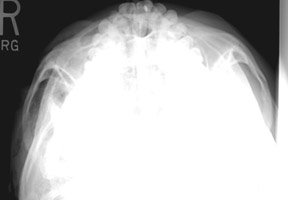

- Click on the image for a larger versionASubmentovertical radiograph. This image of the paranasal sinuses reveals extensive subcutaneous emphysema.